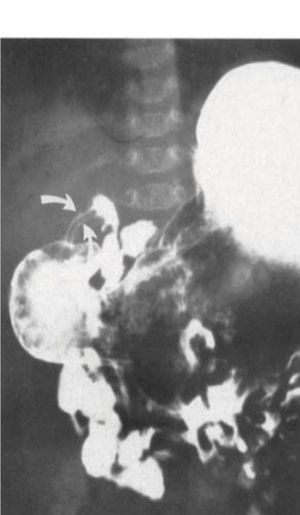

What is ur diagnosis?

Filling defect on barium enema. Possibly due to chron's disease or ulcerative colitis. Chances of malignancy are also there most likely being adenocarcinma colon

But I'll go with adenocarcinoma to be probable diagnosis

What about the fistula?

cisticoduodenal fistula..